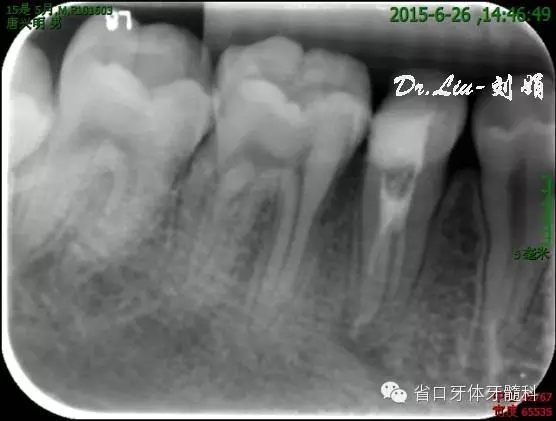

45橡皮障隔離下去封藥,清理根管,沖洗,紙尖干燥根管,拍攝試主尖片,顯微鏡下行熱牙膠根管充填,X線片顯示恰填。

圖9:試主尖

圖10:根充后X線片

圖11:根充后10天樹脂充填修復(fù)